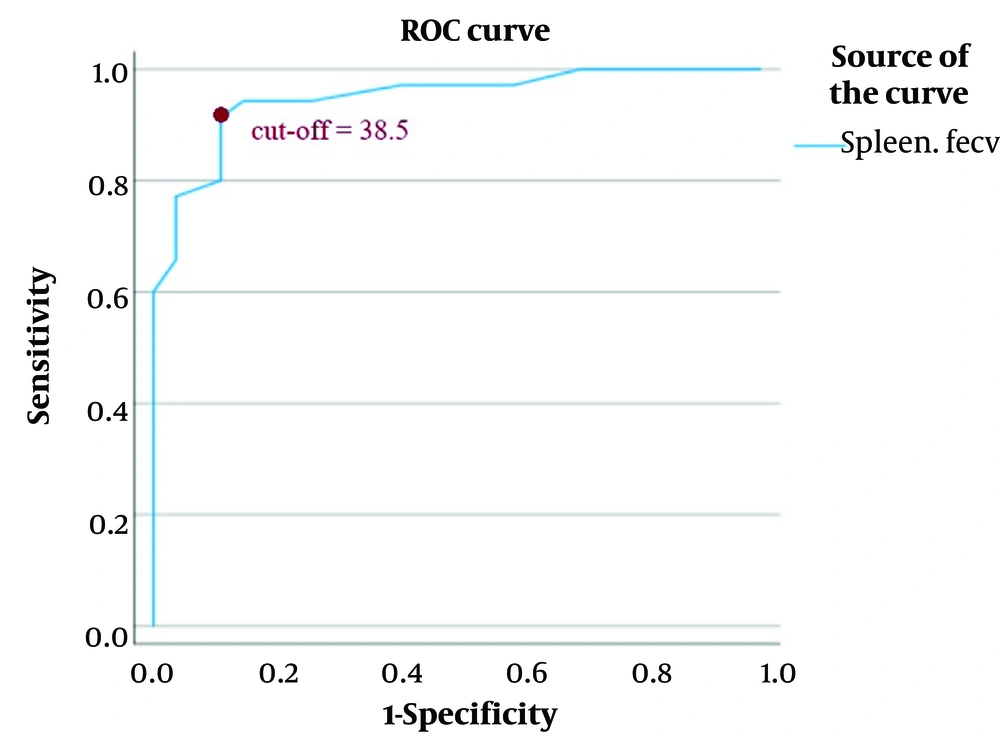

Receiver operating characteristic curve analysis was performed to determine the diagnostic performance of spleen ECV. The optimal cut-off value for spleen ECV was identified at 38.5, yielding a sensitivity of 91.4% (95% CI: 76.9 - 98.2), specificity of 88.9% (95% CI: 70.8 - 97.7), positive predictive value of 92.4% (95% CI: 78.5 - 96.9), and negative predictive value of 95.6% (95% CI: 72.9 - 95.9). The overall diagnostic accuracy was 90.3% (95% CI: 80.2 - 96.4), and the sample's observed prevalence of high-risk varices was 56.5% (95% CI: 43.3 - 69.1). The area under the ROC curve (AUC) was 0.948 (95% CI: 0.896 - 1.000) (Table 3, Figure 5).

Regions of interest (ROIs) curve of spleen extracellular volume (ECV); the optimal cut-off value for splenic ECV (also referred to as fractional ECV or ECV) was identified as 38.5, yielding a sensitivity of 91.4% and a specificity of 88.9%. The positive predictive value was 92.4%, and the negative predictive value was 95.6%. The area under the receiver operating characteristic curve (AUC) was 0.948 (95% CI: 0.896 - 1.000). A direct association was observed between higher splenic ECV values and increased risk of esophageal varices.

Among the variables examined in this study of 62 cirrhotic patients, only splenic ECV (24 out of 35 patients in the HRGscored above the cutoff value), direct variceal visualization on computed tomography (DV-CT) (35 out of 35 patients in HRG were positive), and Child-Pugh classification (23 out of 35 patients in HRG scored C) independently predicted high-risk EGVs. Receiver operating characteristic curve analysis confirmed the diagnostic utility of splenic ECV, with a cut-off value of 38.5, demonstrating strong discriminatory performance.